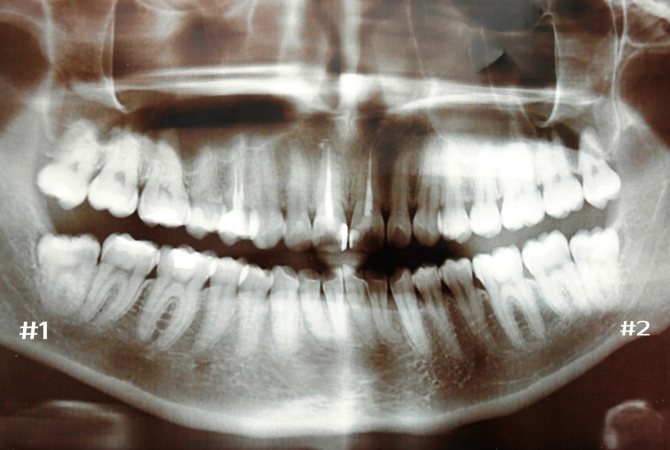

Назначается компьютерная томография и рентгенография. Оба обследования дают проекцию воспаленной области в трех плоскостях.

По снимку специалисту удобно рассматривать и изучать состояние челюстной кости, правильность роста третьего моляра, число корней и особенности их строения.

Наличие снимков помогает врачу принять решение о дальнейших действиях, точно рассчитать время, последовательность и объем предстоящей операции, подготовить нужные инструменты.

Если видно, что третий моляр растет правильно, всегда принимается решение о его сохранении, и тогда удаляются только воспаленные над ним ткани.

Анализ рентгеновского снимка позволит определить расположение зуба мудрости в периодонтальной лунке, выявить кариес и его осложнения, а также исследовать область поражения инфекцией.